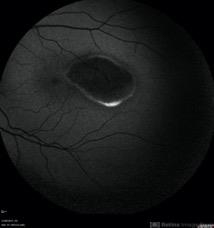

- Torpedo maculopathy

- torpedo maculopathy, fundus autofluorescence (FAF)

- Fundus autofluorescence imaging of an asymptomatic 12-year-old girl with torpedo maculopathy of the left eye.